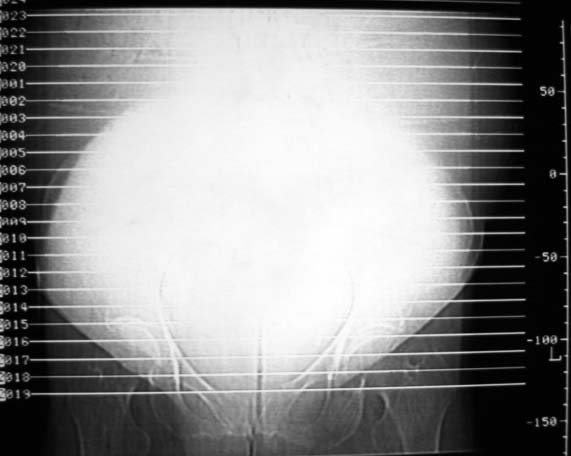

女,75岁,腹部胀大半年余,无其他症状。

考虑来源与卵巢的巨大囊腺瘤或囊肿。

真是腹大如牛,考虑卵巢巨大囊腺瘤或囊肿。

1、考虑卵巢巨大囊腺瘤或囊肿。2、子宫肌瘤不除外。